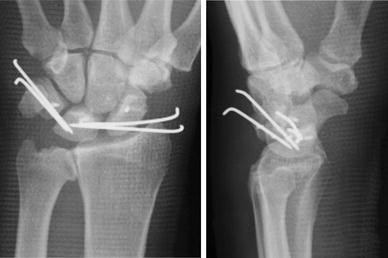

Fig. 2

figure 2

Postoperative radiographs showing good alignment of the carpal bones. The scapholunate angle was 54° and the radiolunate angle 6°. Gilula’s line was well-regulated

A 46-year-old man who fell from a height of 1.5 m onto his left hand was brought to the emergency center of our hospital and underwent a medical examination. Radiography of the wrist revealed palmar-divergent dislocation of the scaphoid and lunate (Fig. 1) but with no neurovascular disturbance in the hand. Two hours after the injury, we performed closed reduction under local anesthesia. Although closed reduction was successful, severe carpal instability was observed. Seven days after the injury, open surgery was performed through the palmar and dorsal approaches. The dorsal approach showed ruptures of the scapholunate and lunotriquetral ligaments, which were sutured with anchors. The palmar approach showed an oblique tear of the anterior capsule, which was sutured with absorbable threads. Finally, the scapholunate and lunotriquetral joints were fixed with two Kirschner wires, inserted from the scaphoid to the lunate and from the triquetrum to the lunate, respectively, and the wires were buried under the skin (Fig. 2). A short arm plaster splint was applied postoperatively; 2 weeks later, it was changed to a removable splint and rehabilitation was started. As Kirschner wires remained in the carpal bones, range of motion (ROM) exercises of the wrist were restricted to avoid wire failure. At 7 weeks, the Kirschner wires and splint were removed, and the patient was started on intensive rehabilitation for an additional 3 months. At the 1-year follow-up, the patient had returned to normal life and work and had no pain in his wrist, although wrist motion was still restricted. Measurements of wrist and forearm ROM showed that right/left extension was 60/50°, flexion was 70/40°, supination was 90/80°, and pronation was 90/90°. A hand dynamometer showed that grip strength in his left hand was 16 kg compared with 27 kg on the contralateral (dominant) side. Although we observed no evidence of dorsal or volar intercalated segment instability pattern deformity, radiography showed a break in arc II of Gilula’s line between the lunate and triquetrum, as well as flexion deformity of the scaphoid (Fig. 3) [8]. Magnetic resonance imaging showed no evidence of avascular necrosis of the scaphoid and lunate (Fig. 4).